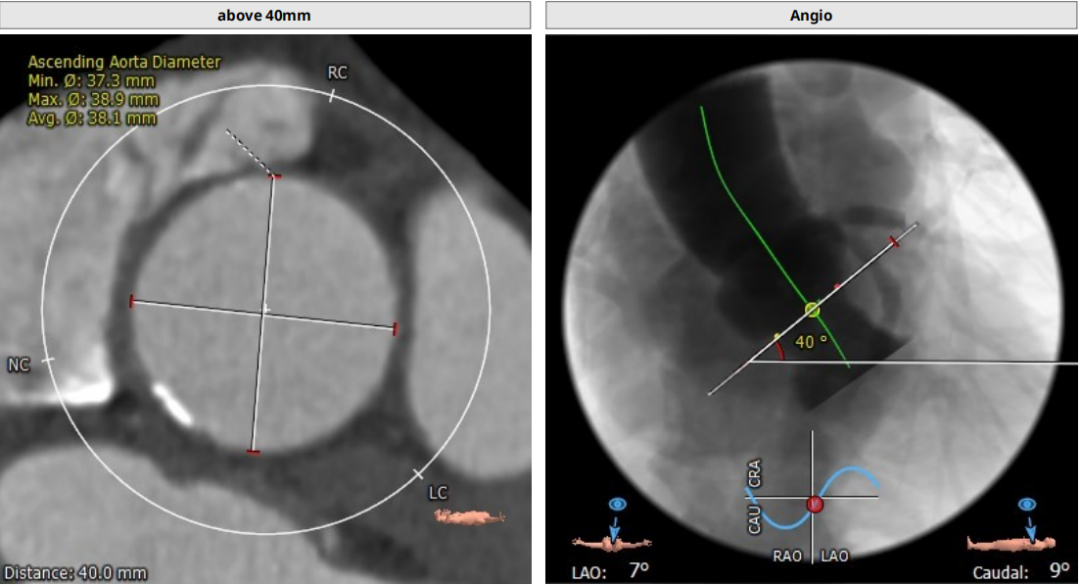

三叶瓣,重度钙化,钙化主要分布在瓣叶游离缘,法式窦结构较大,双冠高度较高,升主动脉未见明显扩张,心脏角度40°,左室大小可,心肌肥厚,主动脉弓部走行较平缓,主动脉弓部可见钙化,过弓轻柔谨慎,以右侧股动脉为主入路。

唐熠达教授团队对病例进行多学科综合分析评估决定行一站式PCI+TAVI手术,结合患者91岁高龄,主动脉根部结构及双侧劲动脉粥样硬化斑块形成,脑动脉硬化情况采用20mm球囊预扩,拟植入VenusA-Valve L26瓣膜。

标准位释放定位